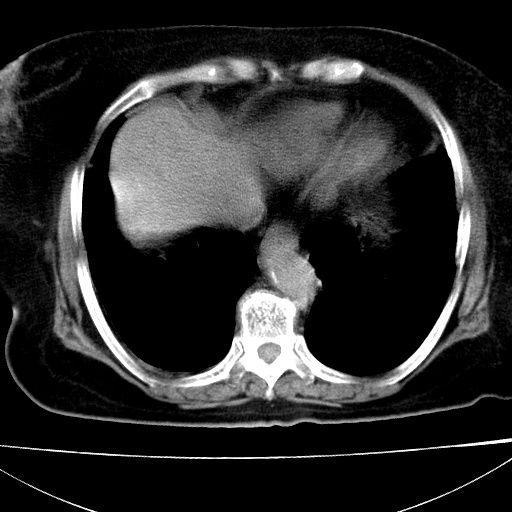

患者女74岁;右上腹胀痛1月,伴恶心,无发热;生活在疫水区。有术后病理及术后半年的追踪ct.

1)慢性血吸虫病(典型)。2)肝硬化。3)肝癌?4)胆囊炎。5)少量腹水。6)右侧少量胸腔积液。

支持.边缘见高密度线条样钙化影.

肝脏体积缩小,肝裂增宽,边缘不平呈波浪状,肝右叶见分隔状条索形钙化,亦见多结节低密度灶,边界不清,肝周可见少许液性暗区,胆囊增大内密度均匀,脾脏下缘低于脏脏的下缘,胸腔亦见液性暗区,余未见明显异常.

诊断:1肝硬化并慢性吸血虫病,脾肿大

2肝内占位,考虑肝癌可能性大,建议做增强

3胆囊炎, 4少量腹水及胸水

胆囊增大饱满,壁增厚。胆囊颈部见软组织密度影。临近肝右叶前段见片状低密度区,病灶下部见条状钙化,少量胸腹腔积液。意见:胆囊颈癌累及肝脏。

病人以胆囊癌手术的,病理结果为中分化腺癌。

现在看看肝右叶内圆形低密度影你们考虑什么呢?

肝内圆形低密度影考虑扩张的胆管

请看3mm重建像如下: